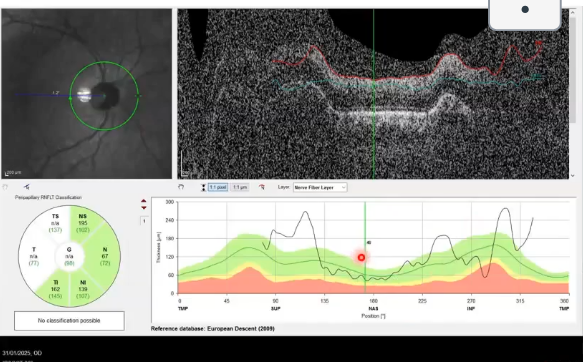

rnfl thickness in an eye with glaucoma

nerve fibre layer thickness falls into the red, so its thinner than 99% of those with normal

would do VFT if red seen

normative da tabases and high myopia

normative databases often exclude high myopes ( more than -5.00 or -600

due to larger eyes/ stretching of ocular structures , tissue profiles may differ from normative database in myopic px